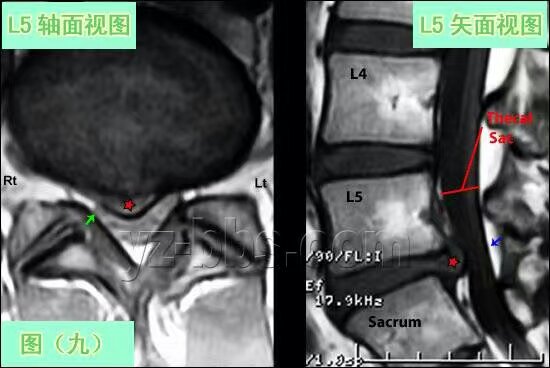

综合性的蜂疗法有效地治疗脊椎间盘突出症 ( 俗称脊椎软骨突出压迫神经线 ),特别是脊椎间盘向外突出压迫了椎管;拔火罐和针灸以松懈压迫的肌肉神经,在脊椎压迫处以美式AMCT调整脊椎,配上意大利蜜蜂蛰刺以达到通经活血消炎止痛,过后再进行中药热敷和艾灸,一星期2至3次的隔天治疗,一般上8至12次为一个大疗程,严重者须3至4个大疗程;如果病患在家配合做日式的义谷疗法,就是躺在床上进行抱膝盖伸展运动,同时服用补肾拉筋和清肝排毒的中药会加速康复,在<<黄帝内经>>中有提到肾主骨和肝主筋,而肝肾又同源,现代医学说明了肝肾是排除固体和水液毒素的主要器官,排毒也是身体自然消炎的机制体现。